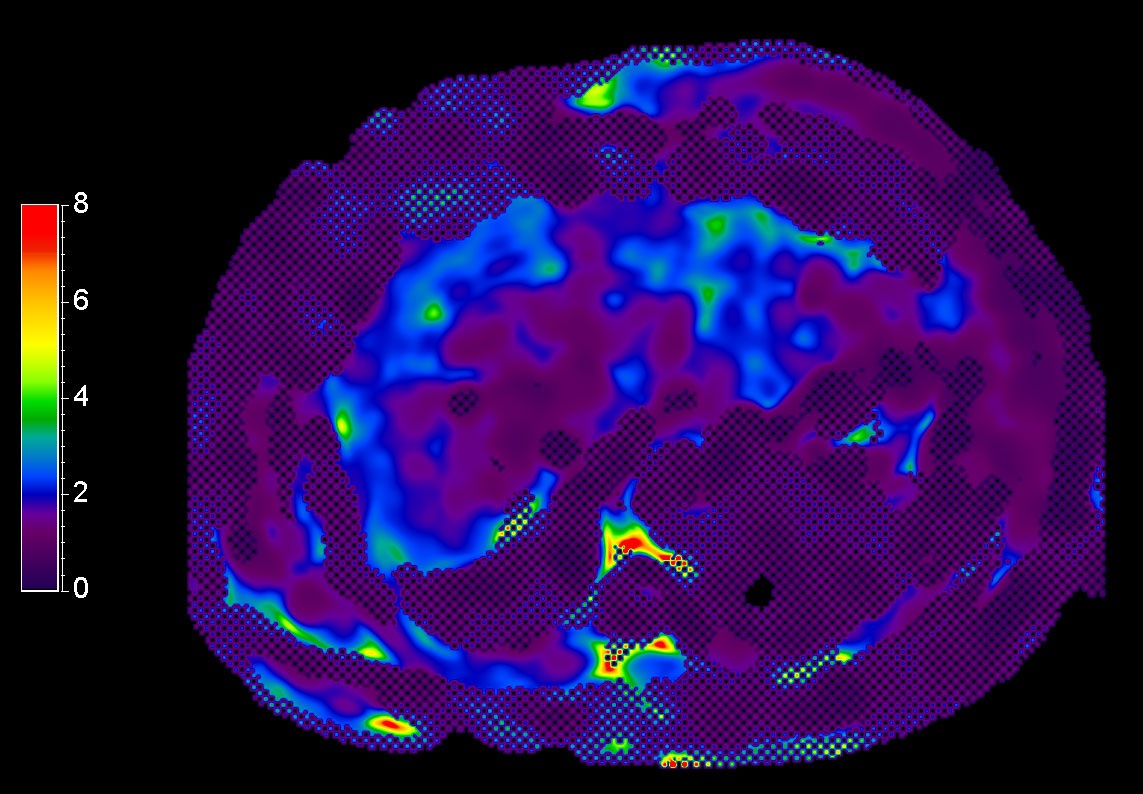

MR Elastography (confidence map) FFE, 18 sec BH/1 slice

MR Elastography (stiffness map) FFE, 18 sec BH/1 slice